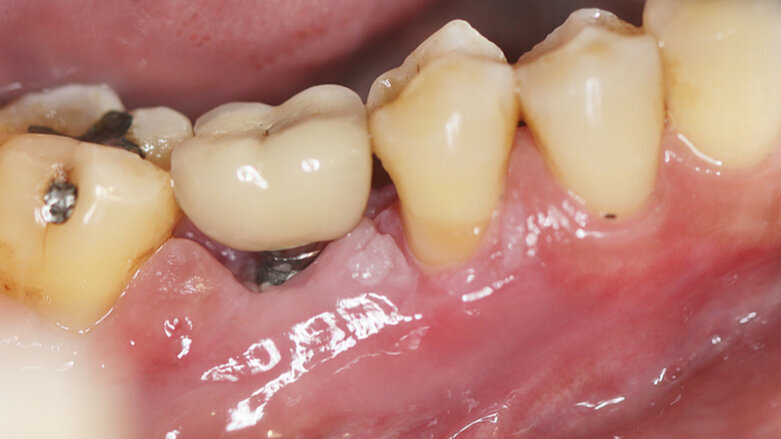

Otprilike kod petina učesnika švedskog istraživanja razvio se peri-implantitis nakon ugradnje implantata. (Fotografija: Kasama Kanpittaya / Shutterstock)

Peri-implantitis je zabeležen kao druga najčešća komplikacija (19,0%). Lečenje bolesti samo nehirurškim metodama, u vidu profesionalnog čišćenja i uputstava o oralnoj higijeni, pokazalo se nedovoljnim. Dodatni hirurški tretman, međutim, uspeo je da spreči dalje napredovanje.